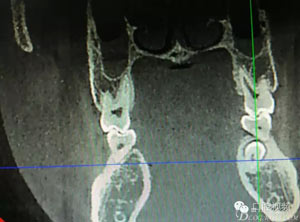

患者、盧xx、男、19歲。主訴:左側(cè)下頜乳磨牙未脫落,要求檢查。??茩z查:左側(cè)下頜第二乳磨牙有充填物。無松動,全景片檢查。35移位至36、37之間。頰舌側(cè)均不能觸及隆起。CBCT檢查:35位于36、37的舌側(cè)。表面骨質(zhì)約2mm左右。35完全骨埋伏,36的遠(yuǎn)中牙根疑是吸收。建議35暫觀察。置留不取?;颊咭蟀纬龘?dān)心壓迫36牙根或者發(fā)生囊性變。術(shù)前簽手術(shù)同意書。

圖2.術(shù)前的CBCT,35移位至36、37之間的舌側(cè)。